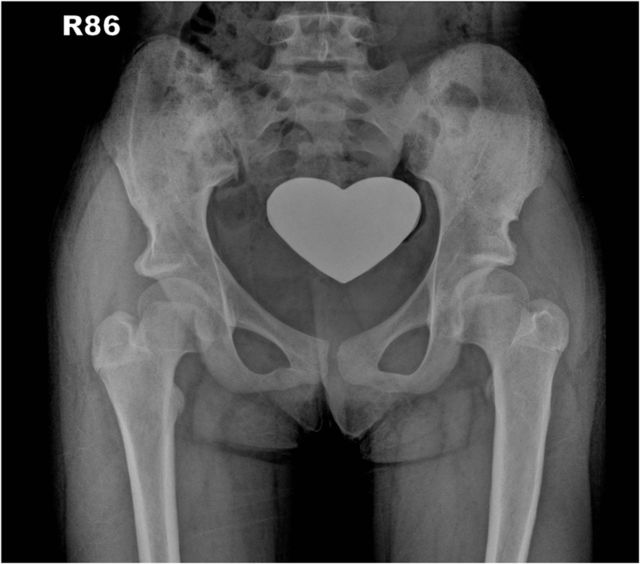

Fig. 29.

Postoperative anteroposterior pelvic radiograph made with the patient wearing a cast after the same procedure on the other side.